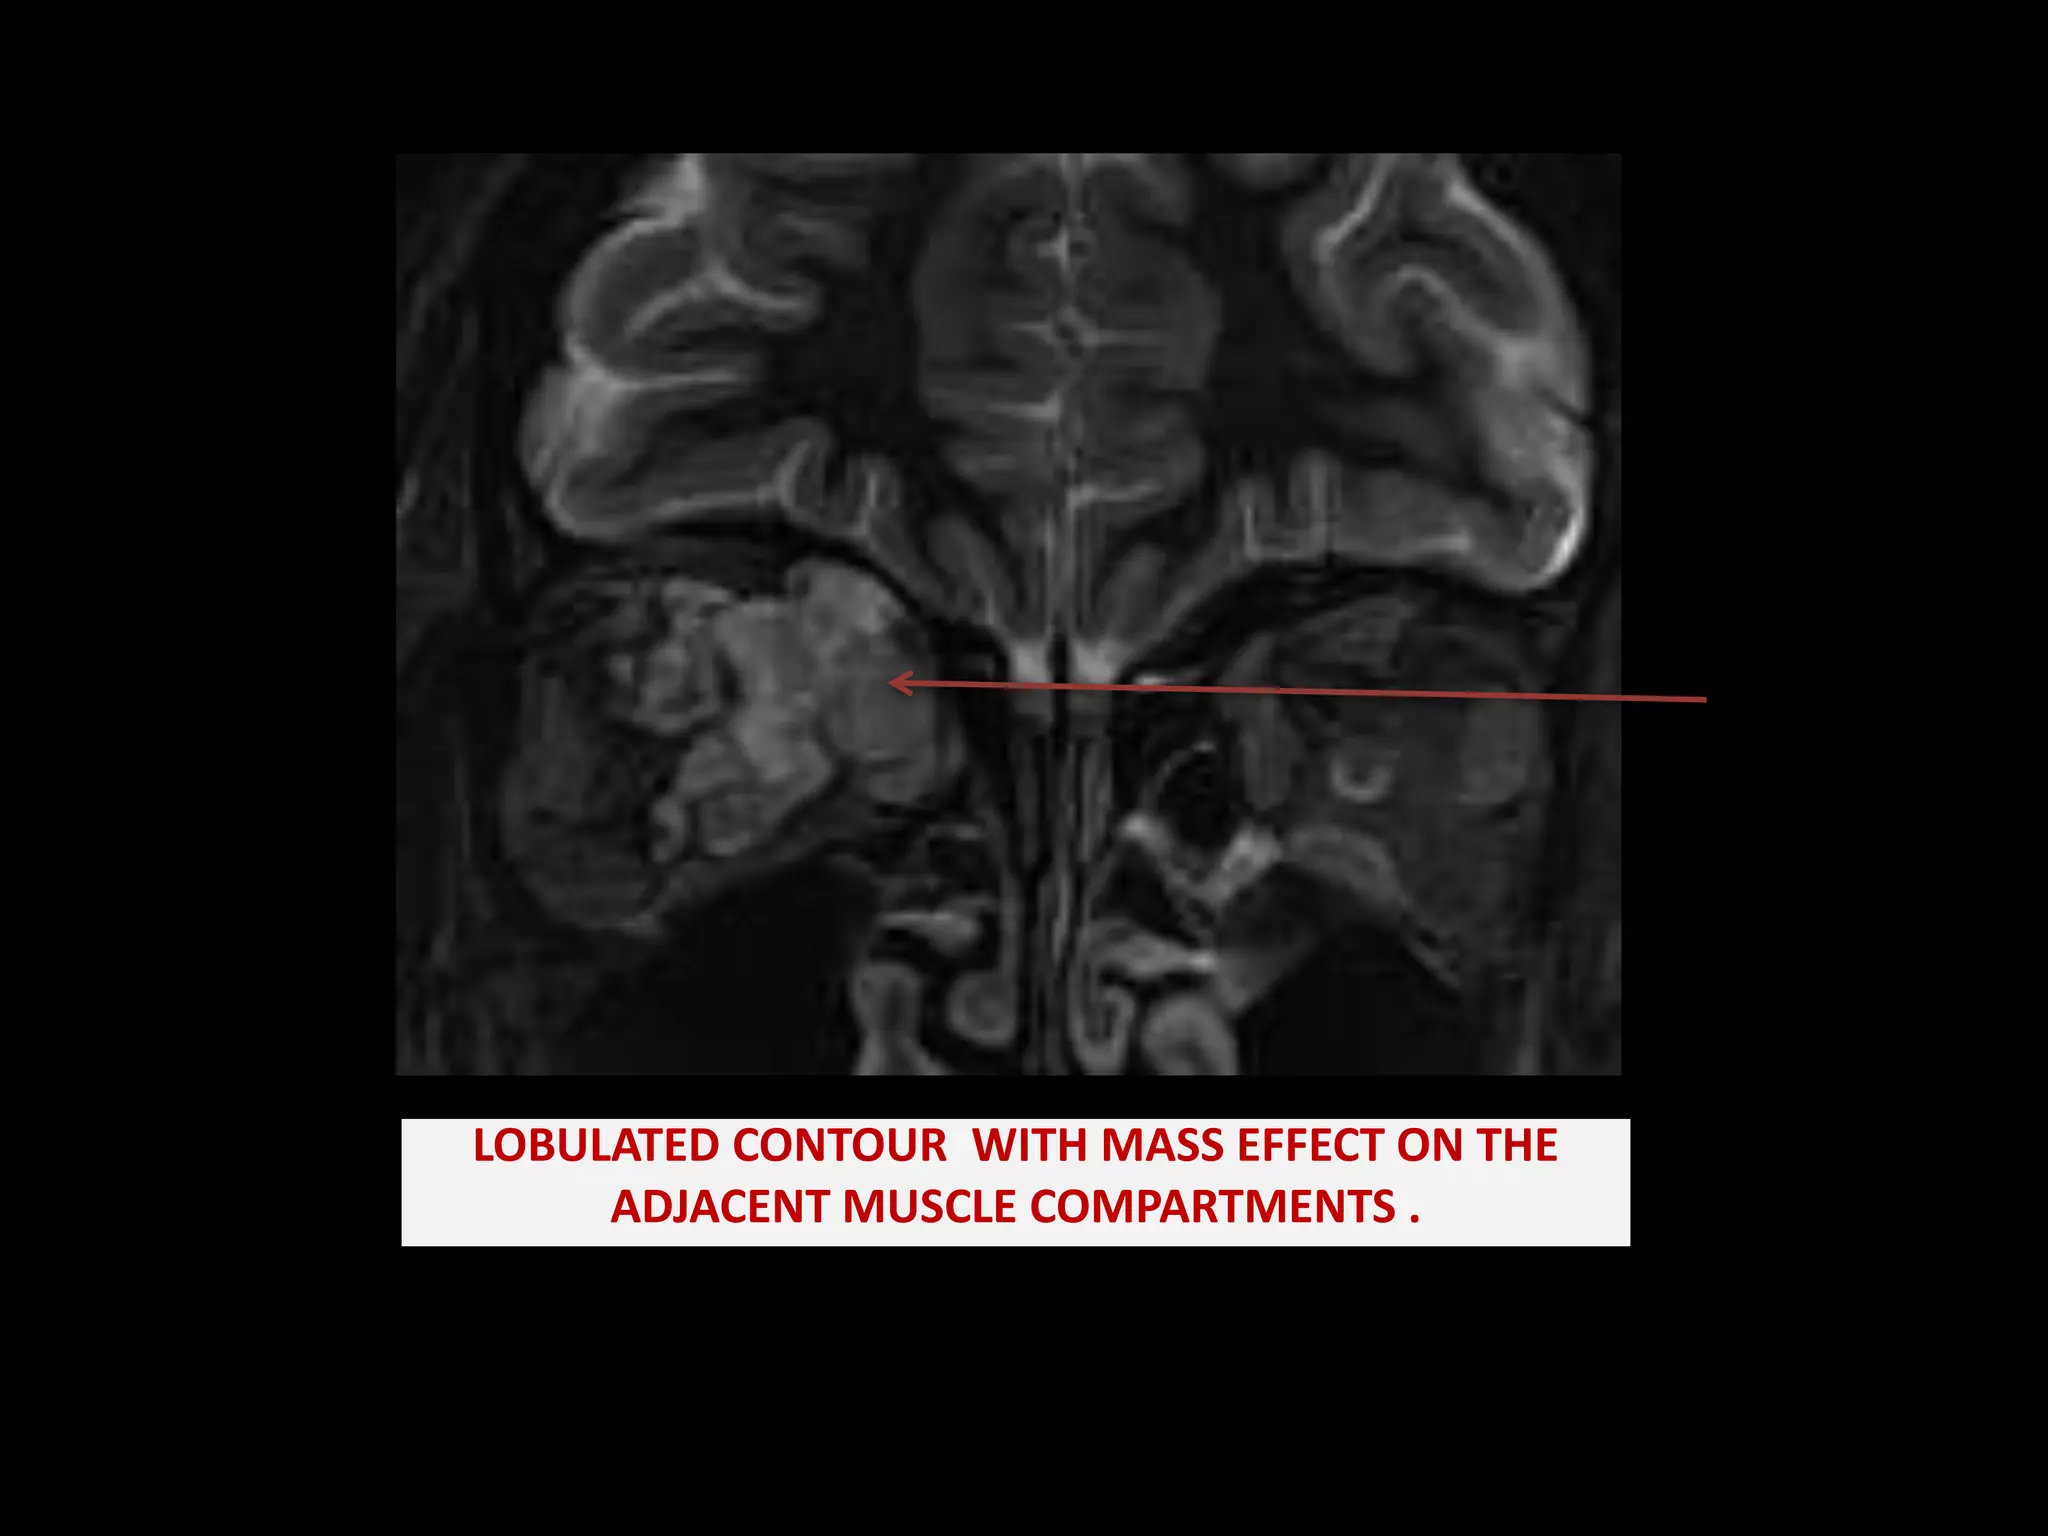

Orbital Lymphatic Malformation (Lymphangioma)

Orbital lymphangioma | PPTX